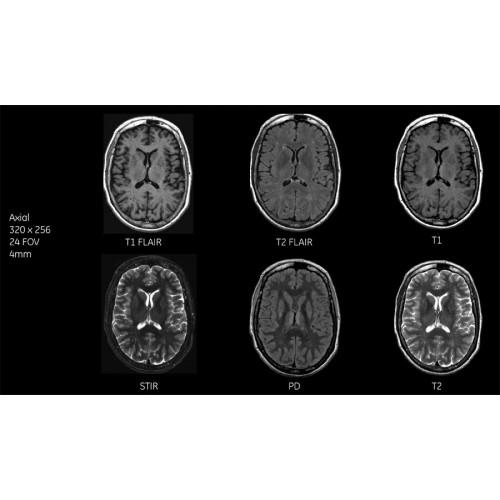

Детализация изображений

Система SIGNA Pioneer воплощает поразительные достижения в области визуализации. Передовая технология Total Digital Imaging (TDI) позволяет добиться большей четкости изображений и на четверть повысить соотношение сигнал/шум.

TDI построена на трех базовых компонентах:

• Технология Direct Digital Interface (DDI) использует независимый аналого-цифровой преобразователь для оцифровки сигнала от каждого из 97 радиочастотных каналов, что обеспечивает значительное увеличение качества за счет уменьшения фонового шума.

• Технология Digital Micro Switching (DMS) — это следующее поколение технологий радиочастотных катушек, основанное на замене аналоговых схем блокировки сверхбыстрыми микропереключателями (MEMS), что делает возможным быстрое переключение катушек для дальнейшего расширения возможностей визуализации с нулевым TE.

• Технология Digital Surround Technology (DST) — это новая технология объемной оцифровки данных, объединяющая сигналы от каждого элемента катушки. Прекрасное соотношение сигнал/шум и чувствительность поверхностных катушек в сочетании с превосходной однородностью и высокой проникающей способностью встроенной радиочастотной катушки — все это позволяет создавать качественные изображения не только позвоночника, но и всего тела.

Помимо технологии 97 РЧ-каналов, SIGNA Pioneer использует магнит 3.0Т высокой однородности, предназначенный для повышения качества визуализации во всех областях, а также закладывающий прочный фундамент для долгосрочных инвестиций и роста клинических возможностей.